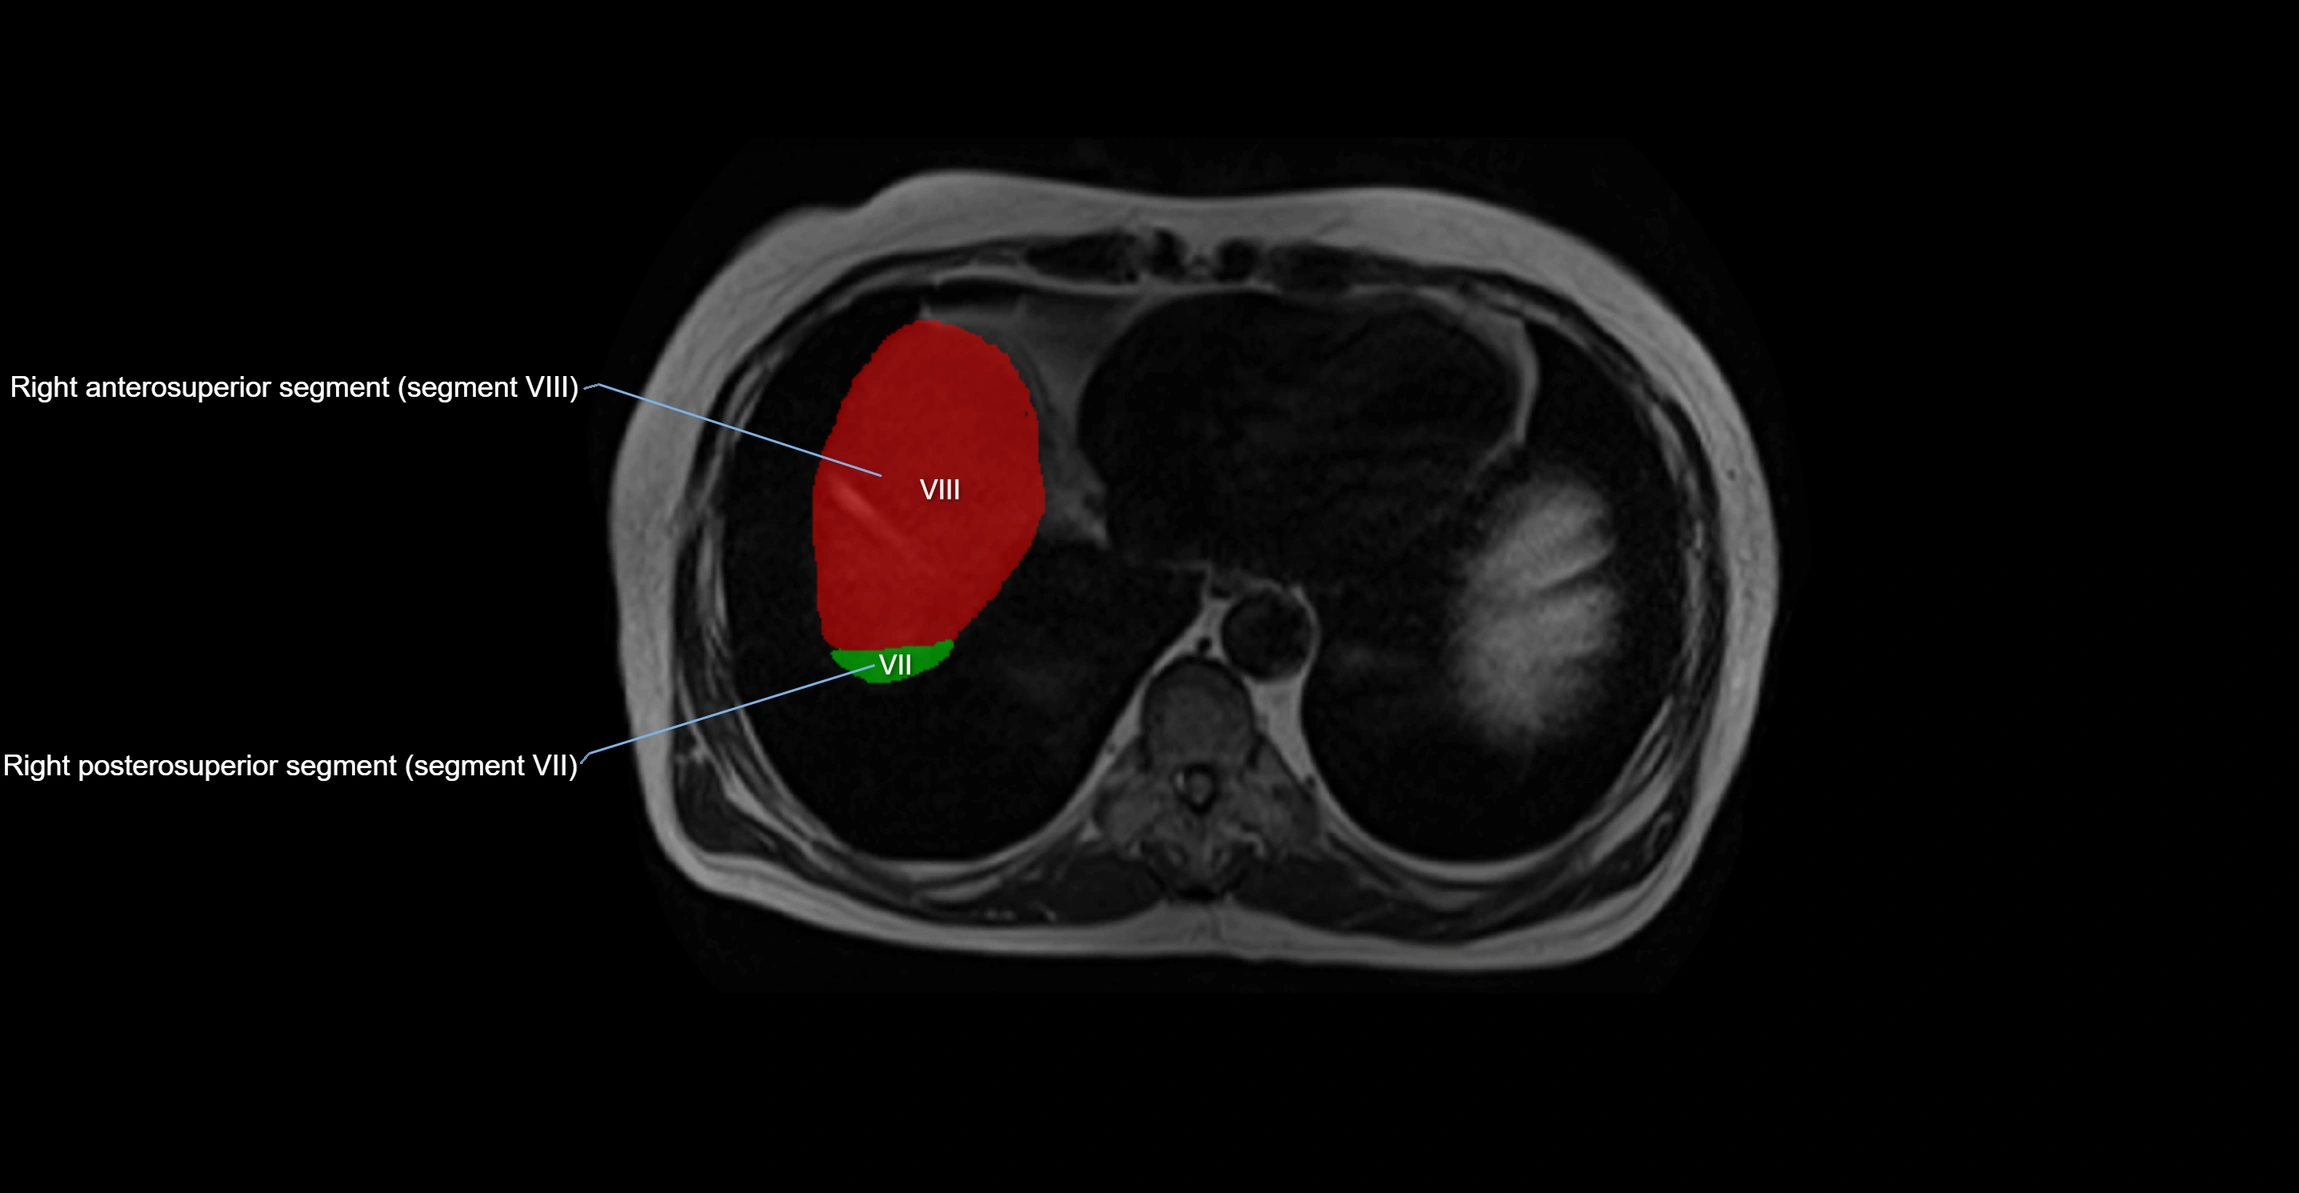

MRI Appearance

T1-weighted images:

• Parenchyma shows intermediate signal intensity, similar to rest of liver

• Lesions (tumors, fat, fibrosis) show altered signal compared to background liver

T2-weighted images:

• Normal parenchyma shows intermediate to slightly hyperintense signal

• Pathologies (cysts, hemangiomas, tumors) demonstrate variable high signal

T1 Fat-Saturated Post-Contrast (Gadolinium):

• Homogeneous enhancement in normal parenchyma during portal venous phase

• Lesions (HCC, metastasis, hemangiomas) enhance with characteristic dynamic patterns

• Important in detecting vascular invasion and caudate hypertrophy